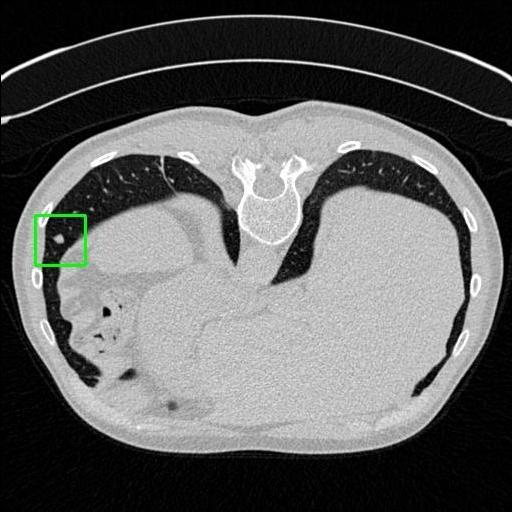

We developed an AI-based system using deep learning models for analyzing lung CT scans to detect and classify pulmonary nodules. We chose the YOLOv11 architecture for its enhanced object detection capability and adapted it specifically for medical imaging, incorporating pixel-level precision and severity classification.

Classification into three severity levels with colored bounding boxes.

Designed a severity classification system that categorizes nodules into null, moderate, and severe using colored bounding boxes, assisting in rapid clinical decision-making.